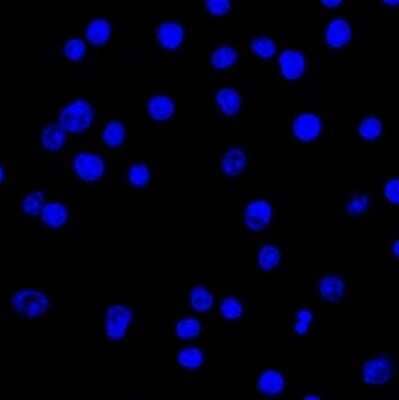

Immunocytochemistry/ Immunofluorescence: Lambda Light Chain Antibody (LcN-2) - Azide and BSA Free [NBP3-11602] - Confocal Immunofluorescent analysis of Ramos cells using AF488-labeled Lambda Light Chain Monoclonal Antibody (LcN-2) (Green). DAPI was used to stain the cell nuclei (blue).